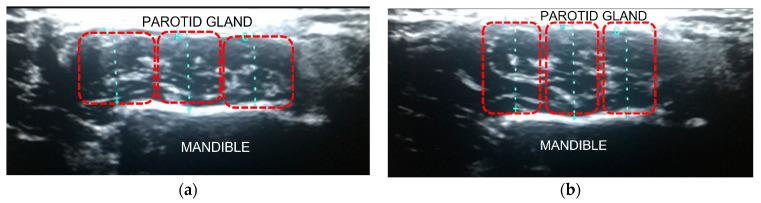

We aimed to investigate whether the collaboration of shear wave elastosonography (SWE) and B-mode ultrasonography (US) could be offered as diagnostic tools to assess the presence, severity, and progress of bruxism, as well as a biomarker for the effectiveness of treatment in daily clinical practice. The study was designed as a quantitative evaluation of the masseter muscles (MMs) of the clinically diagnosed bruxism patients suffering from myofascial pain and MMs of the healthy individuals. Clinical examinations were made according to the diagnostic criteria for temporomandibular disorders (DC/TMD), and pain was assessed using a visual analog scale (VAS). Painful MMs with VAS scores ≥ 4 were assigned to Group A, and healthy MMs were assigned to Group B. Also, the MMs of the painful bruxers were analyzed based on wearing occlusal splints. Group A was divided into two subgroups as splint users (Group AI) and non-users (Group AII). All the participants were scanned with dynamic US and SWE to quantify the size and stiffness of the MMs. Measurements of each muscle pair while the jaw is in a resting position (relaxation) and clenching position (contraction) were recorded. The significant differences in stiffness and thickness became visible in the relaxation state. Bruxism patients with myofascial pain had significantly harder and thinner MMs than healthy individuals. During the relaxation, the mean thickness and elasticity values were 9.17 ± 0.40 mm and 39.13 ± 4.52 kPa for Group A and 10.38 ± 0.27 and 27.73 ± 1.92 for Group B, respectively. Also, stiffer MMs were measured in Group AII (38.16 ± 3.61 kPa) than in Group AI (26.91 ± 2.13 kPa). In conclusion, the combination of SWE and US using a dynamic examination technique has the potential to be a valuable tool for the management of bruxism patients suffering from myofascial pain.